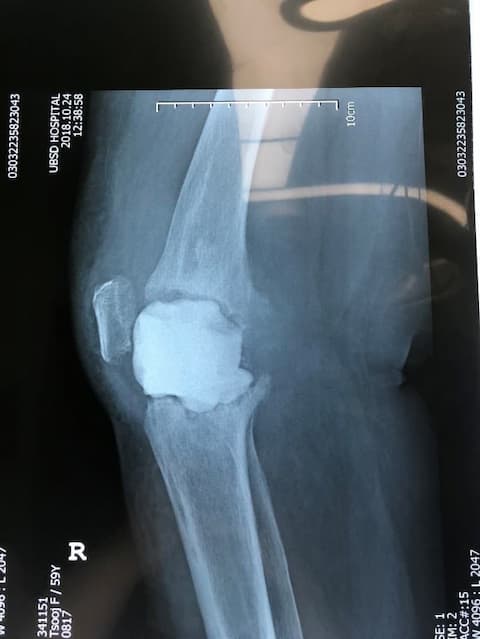

Өвчтөн: П.Ц 60 настай, эмэгтэй 2012.10.23

Үе дайрсан ясны анхдагч хавдар, ясны дутмагшлын үед хийгдэх мэс засалimg37Үе дайрсан ясны анхдагч хавдар, ясны дутмагшлын үед хийгдэх мэс засалimg38

Зураг 1. Сэргээн засах мэс заслын өмнөх рентген зураг. Эгц урд, хажуугаас авсан байдал.